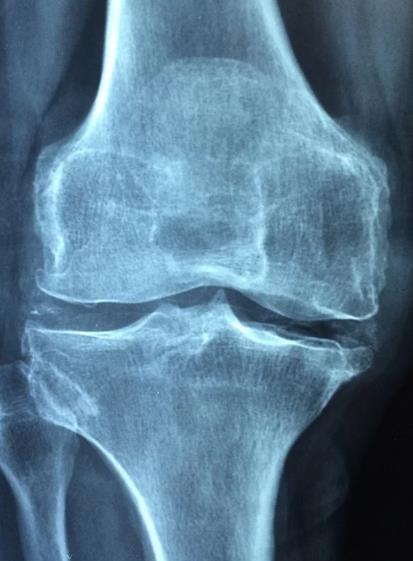

관절염이란

하지만 이런 관절염이 제대로 기능을 못하게 되는경우 여러가지 질환으로 발전하게 됩니다.

가장 대표적은 질환이 관절염입니다. 관절염은 이런 관절에 염증이 생겨 관절에 통증이 발생하게 됩니다.

관절염은 발병 부위에 따라 여러 종류과 있으며 주로 퇴행성관절염인 골관절염과 류마티스 관절염이 있습니다.

퇴행성관절염인 골관절염은 관절의 연골이 닳아 없어져 부분적으로 관절이 퇴행하게 됩니다. 주로 반복적인 운동이나 작업등 오랫동안 무리하여 관절을 사용할경우 발생하게 됩니다.

류마티스관절염은 관절에 있는 활막이 염증반응을 일이키는 경우를 말합니다. 주로 류마티스는 유전적 요인으로 발생하는것으로 봅니다.